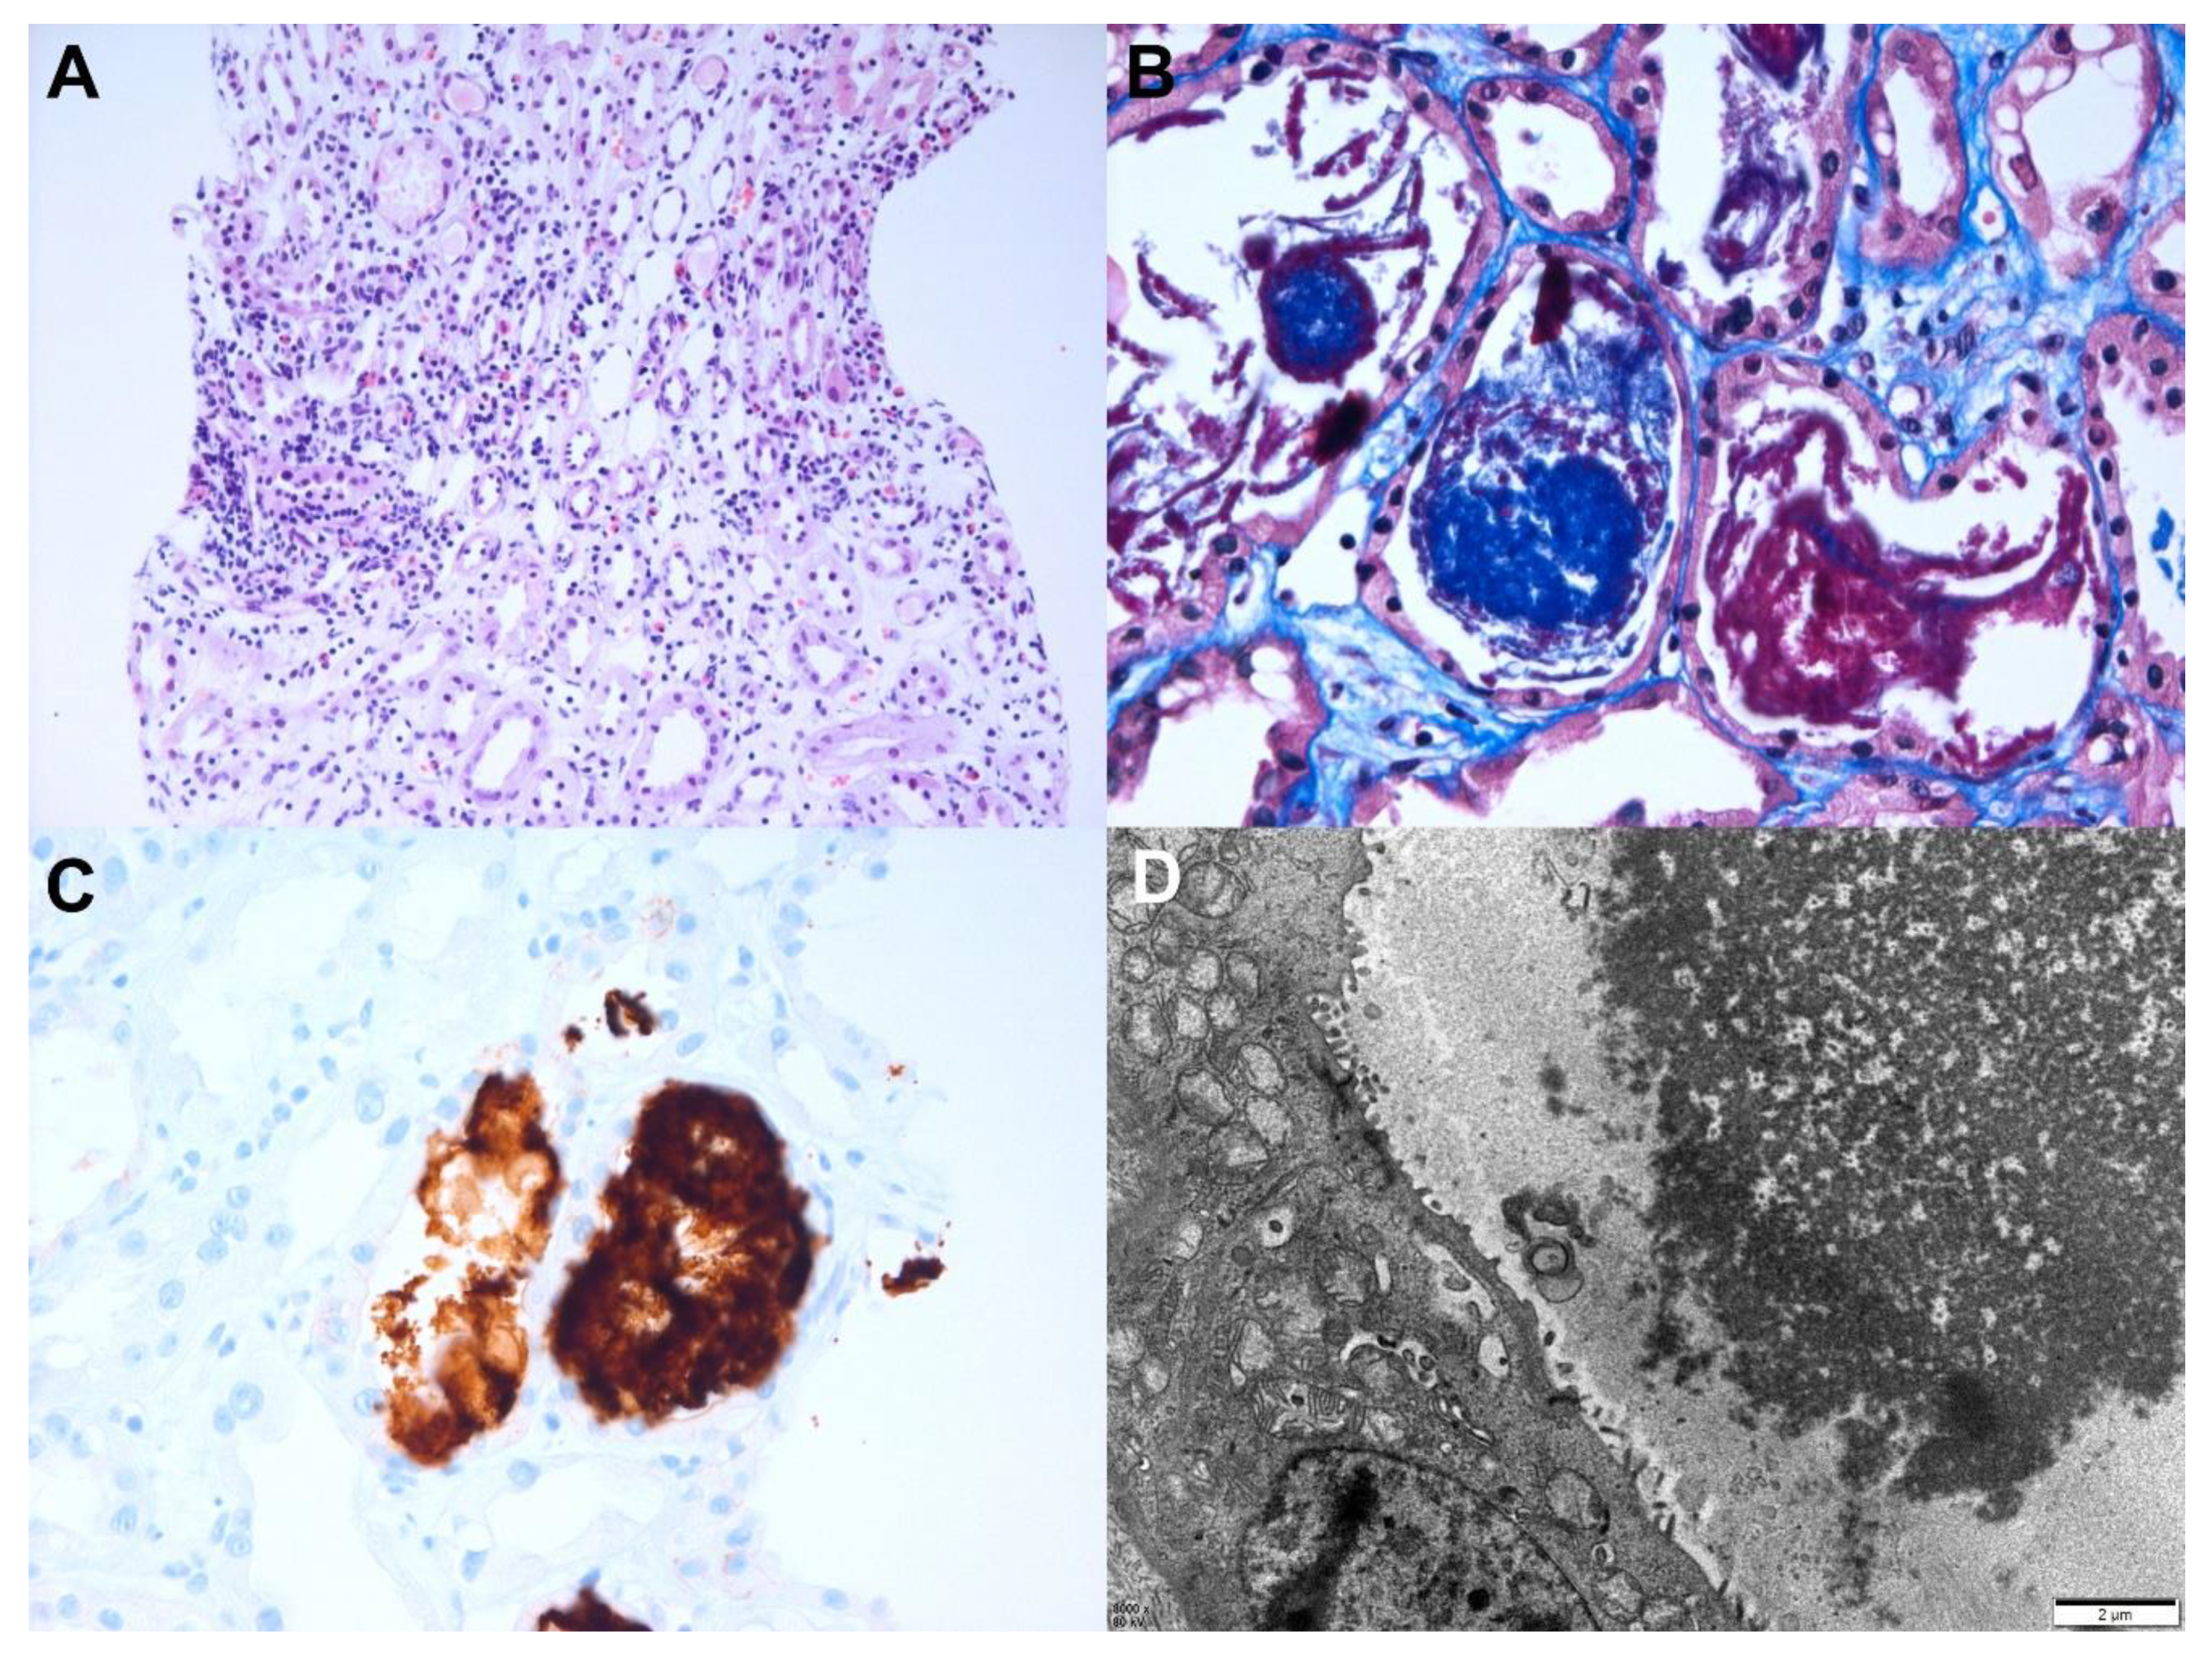

| Chronic thrombotic microangiopathy | 69/F | Acute kidney injury | Type 2 diabetes mellitus | Vector/ AstraZeneca (Cambridge, UK)/ 1st | 2/14 | LM: diffuse thickening of the capillary wall with capillary loop doubling, hyaline thrombi in glomeruli, intact tubules and interstitium, mild infiltration of lymphocytes in the interstitium, arterial fibrointimal thickening IF: fibrinogen 3+ in the glomeruli EM: duplications of the glomerular basement membranes with cellular interpositions, endothelial swelling and hypertrophy with occlusion of the lumens, glomerular intracapillary fibrin deposition with entrapped cellular debris, diffuse foot process loss | 0.80 at 1 year before biopsy | 3.69 | 5.20 | None | SR (21 weeks) |